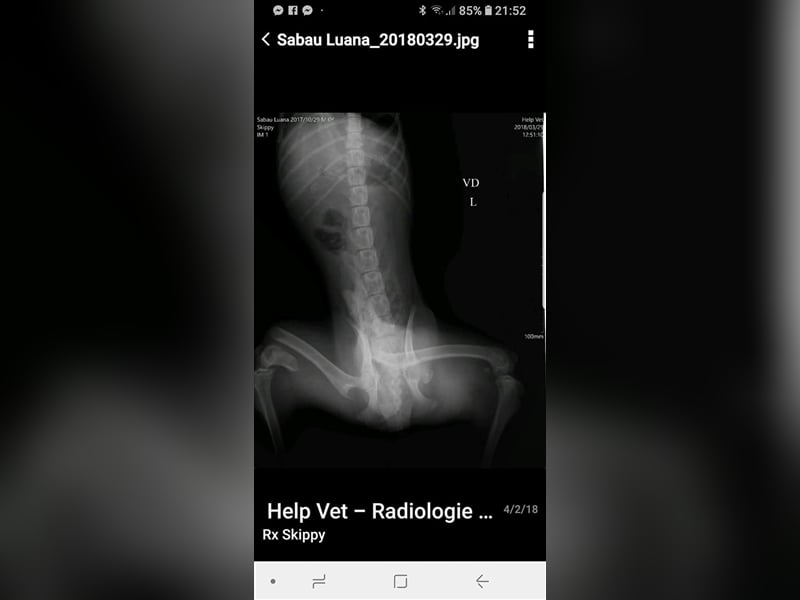

Skipper wurde im Oktober 2017 geboren, hat eine Schulterhöhe von knapp 50 cm und ist kastriert. Der Rüde wurde verletzt im Straßengraben gefunden, beide Hinterbeine waren gebrochen, doch er konnte erfolgreich operiert werden. Er ist inzwischen wieder flott auf seinen vier Beinen unterwegs, auch wenn sein Bewegungsablauf nicht ganz rund ist, so schränkt ihn seine minimale Behinderung nicht ein, fällt auch kaum auf und er ist auf seinen vier Beinen flott unterwegs. Der hübsche Rüde wird vielleicht nicht der ideale Begleiter für längere Joggingrunden oder Radtouren sein, aber nicht jeder Mensch ist ein Sportfreak und Skipper ist auf keinen Fall ein Couchpotato. Skipper lebt seit Juli bei einer Pflegefamilie in Dortmund zusammen mit anderen Hunden und kann dort gerne kennengelernt werden.

Skipper wurde im Oktober 2017 geboren, hat eine Schulterhöhe von knapp 50 cm und ist kastriert. Der Rüde wurde verletzt im Straßengraben gefunden, beide Hinterbeine waren gebrochen, doch er konnte erfolgreich operiert werden. Er ist inzwischen wieder flott auf seinen vier Beinen unterwegs, auch wenn sein Bewegungsablauf nicht ganz rund ist, so schränkt ihn seine minimale Behinderung nicht ein, fällt auch kaum auf und er ist auf seinen vier Beinen flott unterwegs. Der hübsche Rüde wird vielleicht nicht der ideale Begleiter für längere Joggingrunden oder Radtouren sein, aber nicht jeder Mensch ist ein Sportfreak und Skipper ist auf keinen Fall ein Couchpotato. Skipper lebt seit Juli bei einer Pflegefamilie in Dortmund zusammen mit anderen Hunden und kann dort gerne kennengelernt werden.